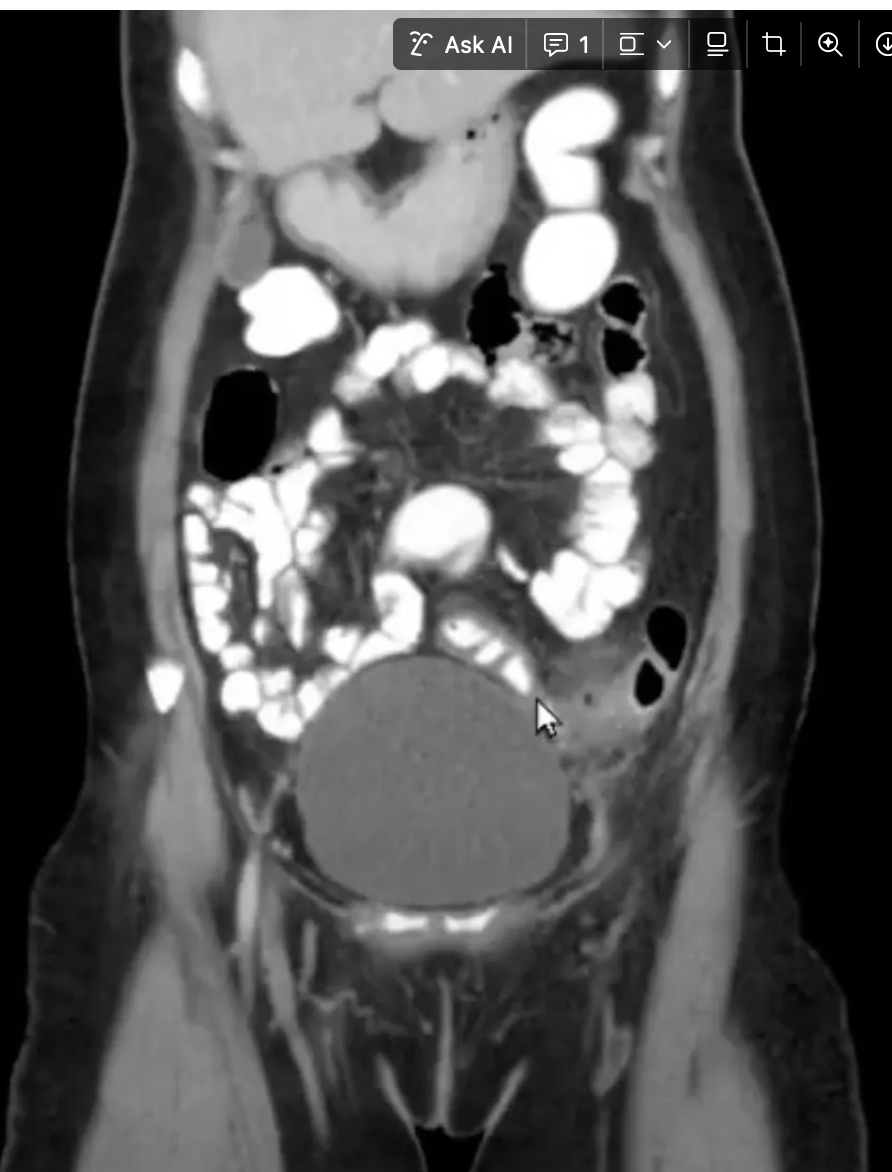

Q

Achado?

A

VÁRIOS DIVERTÍCULOS EM COLON DE PAREDE ESPESSADA E BORRAMENTO DE GORDURA

OS DIVERTÍCULOS SÃO AS BOLINAHS COM INTERIOR PRETO E AO REDOR BRANCO